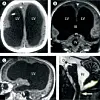

Researchers have found significant increases in the hippocampus, a structure deep in the cortex, after three months of intensive language learning.

The hippocampus serves as a short-term holding area for memories before they are stored as long-term memory elsewhere in the brain.

The structure also helps us orient ourselves spatially in our environment.

The researchers have also discovered growth in three other areas − linked to language acquisition − in the cerebral cortex among recruits enrolled in an intensive language study programme.